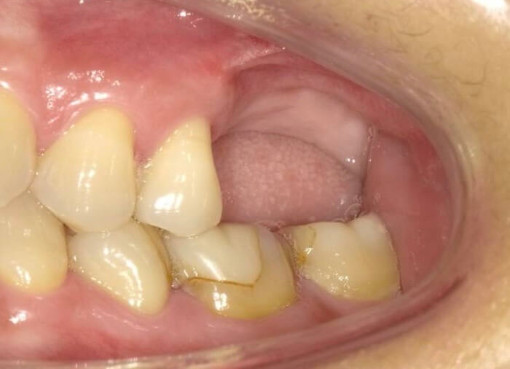

自然で美しい見た目を叶える治療

インプラント周囲の歯ぐき(歯肉)にもこだわり、自然で調和の取れた仕上がりを追求。審美的な美しさを大切にした治療を行っています。